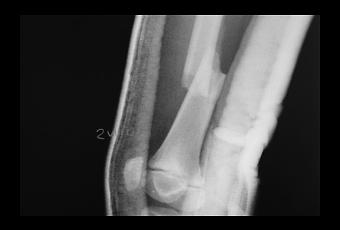

- Radiografía para analizar con la máxima precisión el daño interno.

- Consulta a los especialistas para garantizar la corrección del diagnóstico.

- Aplicación del tratamiento más adecuado para reparar el daño y evitar secuelas.

- Someterse a las necesarias revisiones para comprobar que el tratamiento está funcionando o, en caso necesario, corregirlo a tiempo.

- Rehabilitación para devolver la movilidad a la zona fracturada.